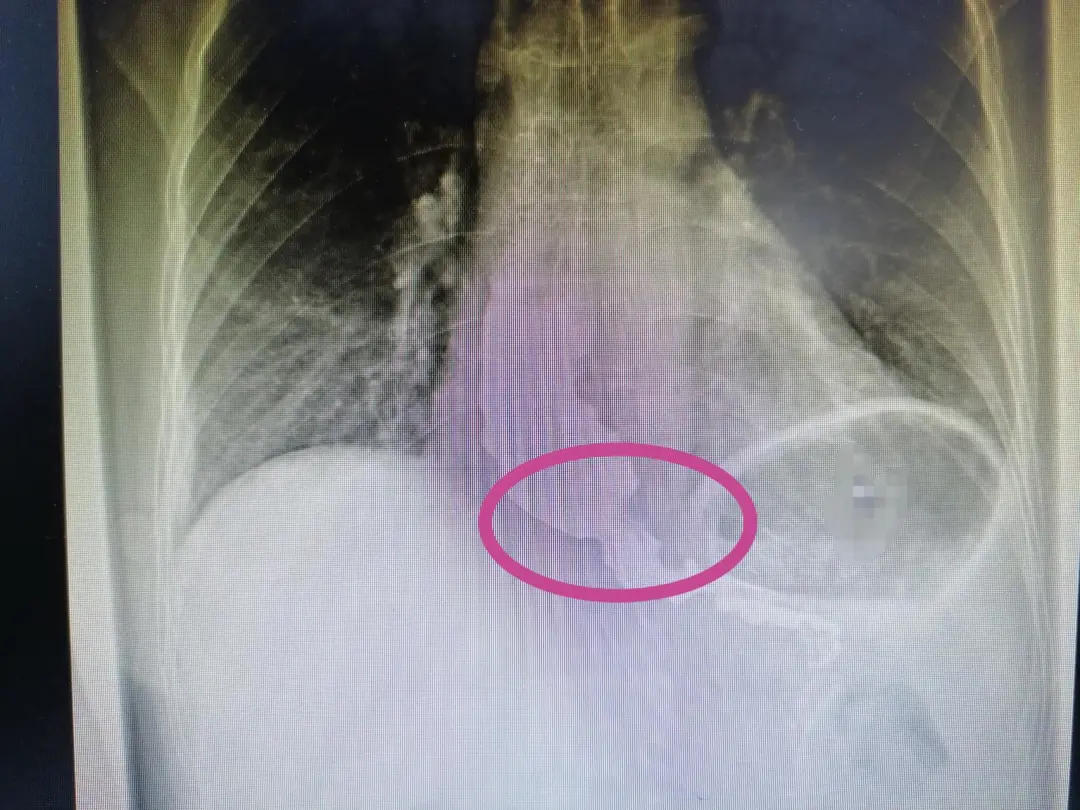

据何恒正教授介绍,“贲门失迟缓症”是一种食管神经肌肉功能障碍性疾病,又称“巨食管症”,该类患者的食管下端括约肌缺乏蠕动或收缩、迟缓不良或无松弛,导致吞咽时食管体部及食管下端括约肌区压力升高,患者钡餐影像呈特征性的“鸟嘴征”。近年来腔镜技术的发展,腹腔镜下食管下段括约肌切开术联合抗反流措施是当前治疗贲门失迟缓症的最佳选择,具有创伤小、术后恢复快、痛苦小、住院日短、术后胃食管反流发生率低等优点。